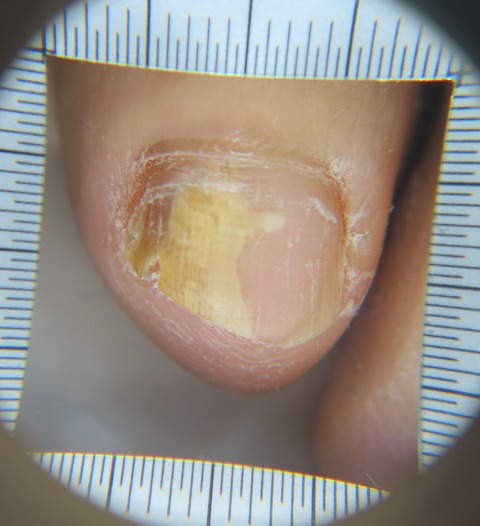

写真の様に皮膚が壊れて深い部分まで損傷している場合に用います。

肉芽や上皮の再生を促してくれる外用薬です。